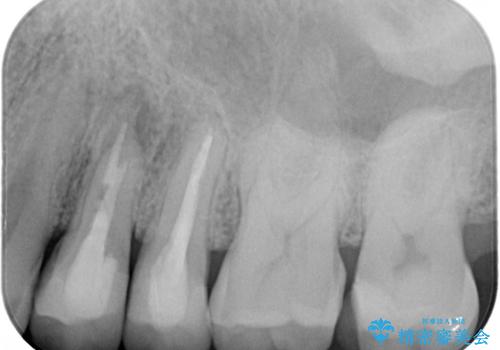

左上の仮歯を2年使用して穴があいて外れたことをきっかけにご来院されました。

レントゲン上からも、歯の中(根管)が汚れている可能性があることをご説明したところ、根管治療からやり直しをすることになりました。